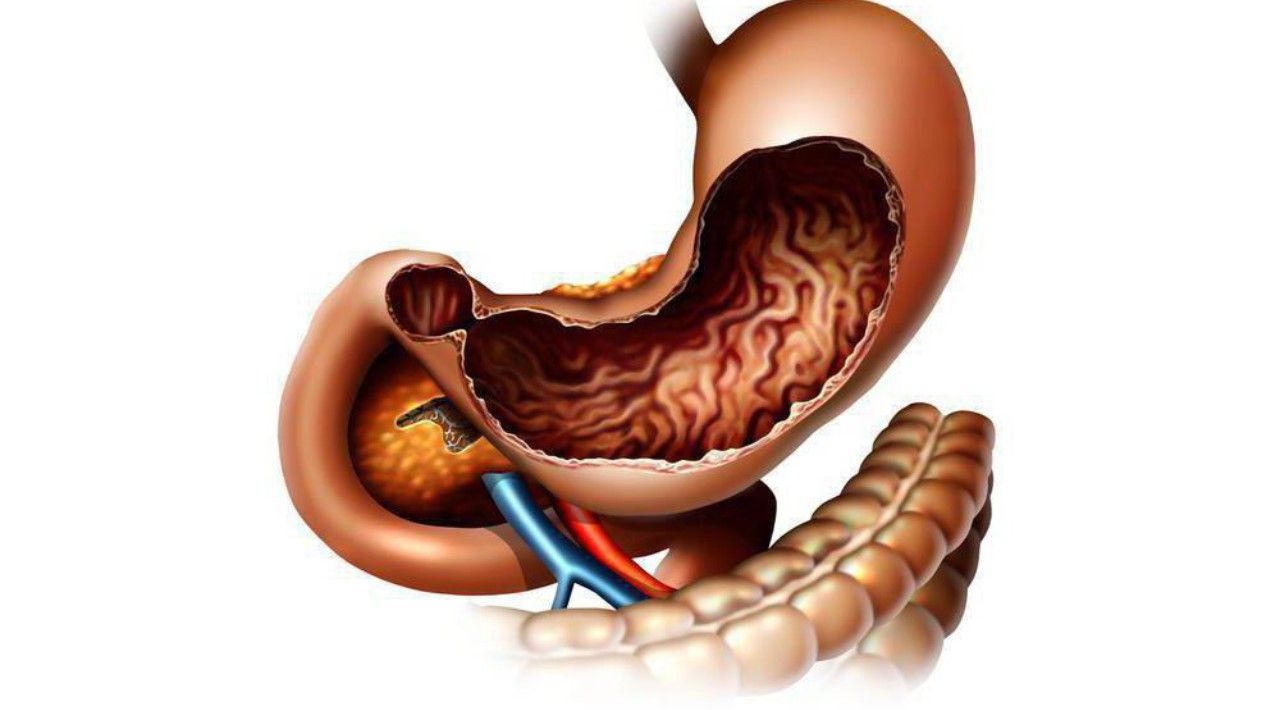

Информация и фотографии о хроническом гастрите и дуодените